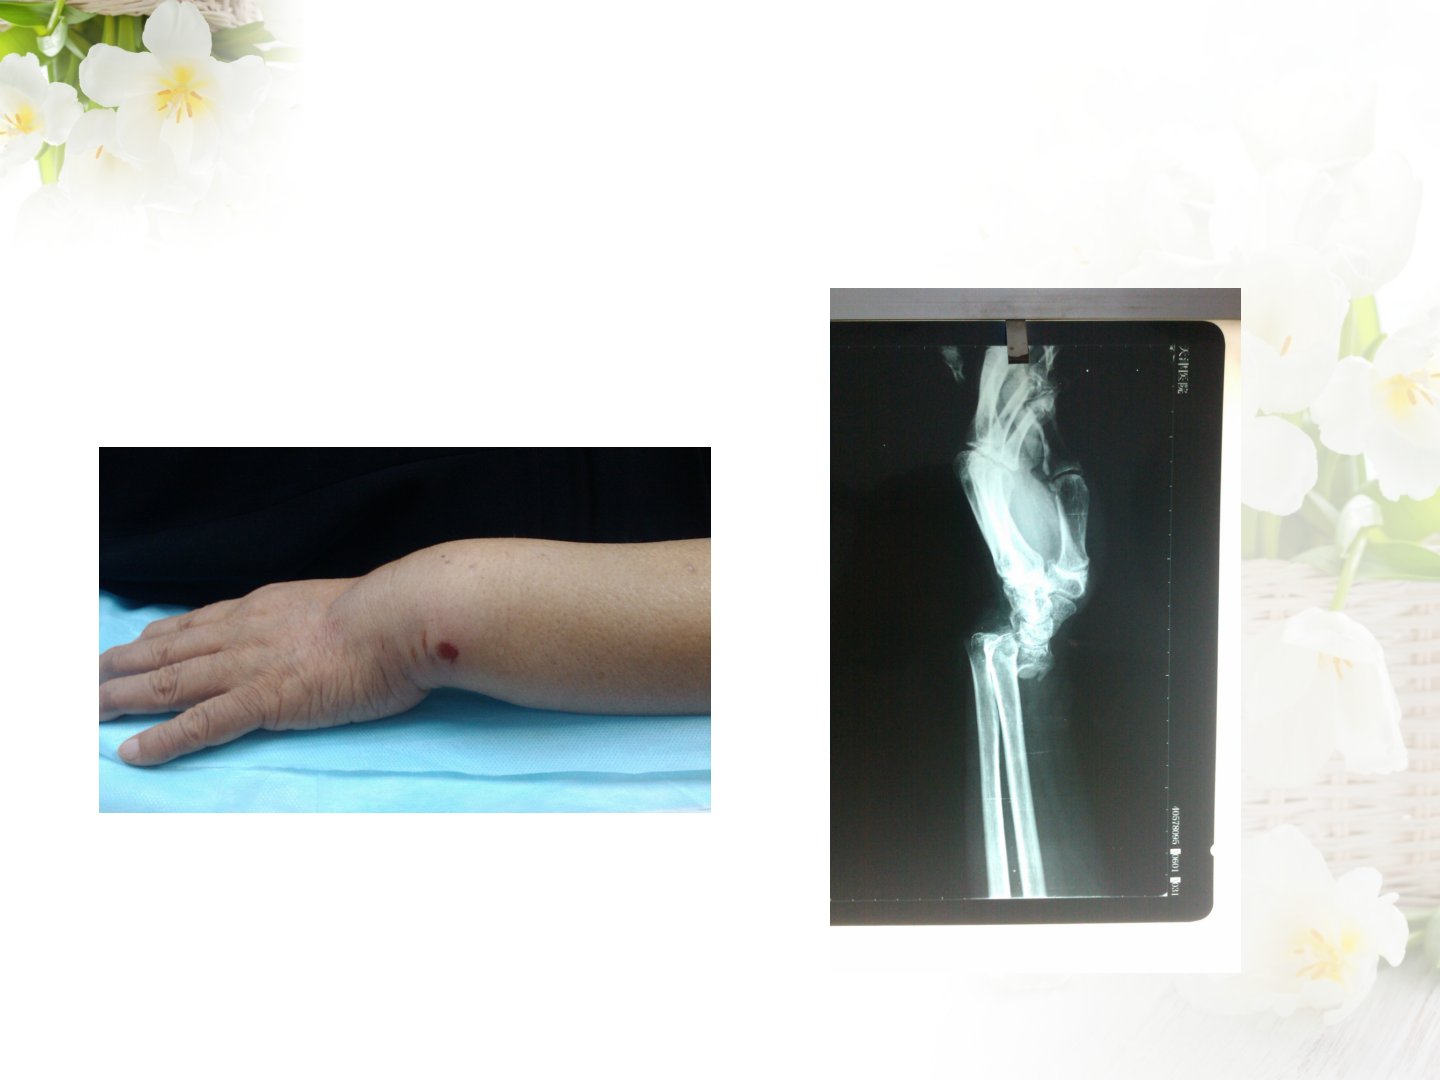

摘要骨折指骨的完整性和连续性中断症状包括疼痛、肿胀等一般情况以及畸形、异常活动等特殊体征X线检查可明确部位、移位类型和愈合情况。骨折愈合经历出血发炎、修复改建等时期分为纤维骨痂期、骨性骨痂期、临床愈合期和骨性愈合期。骨折可根据原因、程度、是否与外界相通、骨折端稳定程度进行分类。骨折并发症包括早期休克、脂肪栓塞综合症等和晚期压疮、下肢静脉血栓等。骨折临床愈合标准包括局部无压痛、无异常活动等。临床治疗原则包括复位固定和功能锻炼复位注意事项包括早期、有效、无痛及少创复位。影响骨折愈合的因素包括全身因素和局部因素。康复评定主要考虑主观检查、物理检查等康复治疗作用包括促进肿胀消退、防止关节挛缩等。康复治疗原则需考虑患者情况制定康复计划康复治疗方法包括急性期消肿、防止肌肉萎缩以及亚急性期及慢性期恢复关节活动范围和肌力。